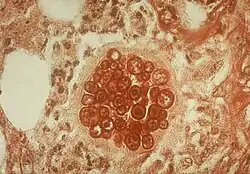

| Histopathological changes in a case of coccidioidomycosis of the lung showing a large fibrocaseous nodule. | |

Spherule and endospore forms of Coccidioides immitis

Spherule and endospore forms of Coccidioides immitis -

Mature spherule with endospores of Coccidioides immitis

Mature spherule with endospores of Coccidioides immitis